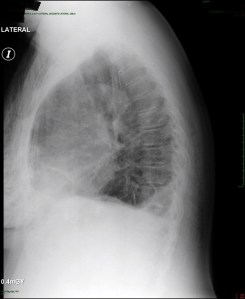

Post-operative:  Post-operative chest x-ray confirmed appropriate chest tube placement and no significant bleeding or pneumothorax.

Immediate post-operative film (chest tube visible)

PA & LAT films on post-operative day 2

pod2